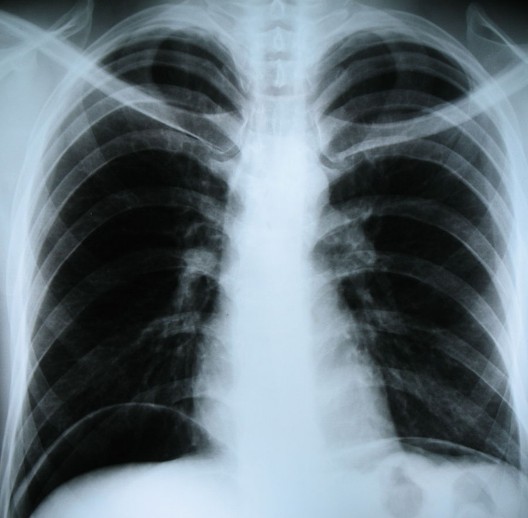

Отличие КТ, МСК, УЗИВ основе обоих методов лежит рентгеновское излучение. Рентгенография имеет ряд преимуществ перед КТ – она более доступна, имеет низкую стоимость и характеризуется более низкой лучевой нагрузкой. Рентген в основном применяется как первичный скрининг для выявления травматических изменений костей и суставов, а также воспалительных и инфекционных процессов пазух носа, грудной клетки и внутренних органов.  Рентген и флюорография не позволяют проводить трехмерную реконструкцию снимков.

В отличие от рентгена КТ позволяет получать детализированные и подробные снимки не только костей, но и мягких тканей, выявлять и дифференцировать патологические процессы незначительных размеров.